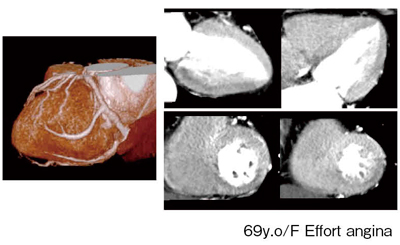

69歳,女性の症例では,冠動脈CTによりRCA,LADの近位部にきわめて強い石灰化が認められた。冠動脈CTでは内腔の評価はまったくできなかったため,Dynamic CTPを施行した。心臓の上から4cm,下から4cmを交互に撮影し,これらを組み合わせることで任意断面を見ることのできるDynamic CTPのボリュームデータが得られる(図6)。短軸方向の画像を見てみると,下壁に明らかな血流異常が認められた。

図6 Stellar DetectorによるDynamic CTPの画像